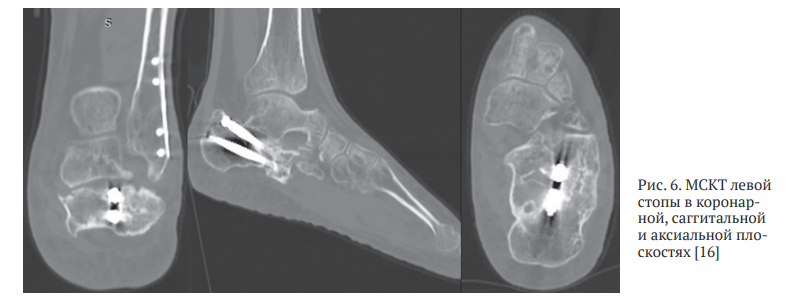

Для уточнения хода линий перелома, взаиморасположения и степени консолидации фрагментов пяточной кости пациенту выполнена МСКТ левой пяточной кости, в ходе которой подтвержден исходный суставно-депрессионный характер перелома, выраженный пяточно-малоберцовый конфликт, а также уточнены форма и взаиморасположение консолидированных фрагментов пяточной кости и металлоконструкций (рис. 6).